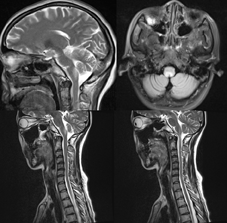

患者女性,39岁,因上腹部不适、恶心呕吐、乏力20余d以"电解质紊乱"于2016年2月24日入住我院内分泌科,在此住院之前因顽固性呕吐曾就诊于当地县医院、某省级三甲医院,曾查过血钾,结果偏低,因此予以止吐、补液、补充电解质等对症治疗,均无效。入院体检:意识清楚,精神差,体检欠合作。皮肤黏膜无黄染及出血点,浅表淋巴结无肿大。眼睑无浮肿。颈软。心肺未闻及异常。腹部平软,无压痛,肝脾未触及。双下肢无水肿。入院诊断:电解质代谢紊乱,经补液、抑酸等治疗无明显好转。入院后第4天出现构音不清、吞咽困难,乏力明显。于2016年3月2日转入我院神经内科进一步治疗。转入体检:意识尚清,精神较差,消瘦,言语不清,双眼视力粗测基本正常,双侧眼球垂直性眼震,咽反射减退,双肺呼吸音粗,无干湿啰音。心律规整,无杂音。右侧肢体肌力减退(Ⅳ级),右侧偏身浅感觉减退。病理征未引出,脑膜刺激征阴性。辅助检查:血常规:白细胞6.93×109/L(正常值3.5~9.5×109/L),血红蛋白125 g/L(正常值115~150 g/L),血小板184×109/L(正常值125~350×109/L);红细胞沉降率37 mm/h(正常值0~20 mm/h);尿常规:外观淡黄色,尿胆原(+),尿酮体(+++),隐血(-),尿蛋白(-),尿糖(+++),尿白细胞(-),尿pH=7.0(正常值4.6~8.0),尿比重1.022(正常值1.003~1.030),病理管型0.3个/μl(正常值0~2个/μl)。碳13呼吸试验示幽门螺杆菌阳性(正常阴性)。血生化:钾2.90 mmol/L(正常值3.5~5.3 mmol/L),钠133.5 mmol/L(正常值137~147 mmol/L),氯100.7 mmol/L(正常值99~110 mmol/L),钙2.40 mmol/L(正常值2.03~2.54 mmol/L),磷1.57 mmol/L(正常值0.9~1.34 mmol/L),阴离子间隙20.09 mmol/L(正常值8~16 mmol/L),CO2 16.2 mmol/L(正常值22~29 mmol/L),血尿素氮5.82 mmol/L(正常值2.9~8.2 mmol/L),肌酐48.6 μmol/L(正常值53~97 μmol/L),尿酸185.7 μmol/L(正常值155~357 μmol/L),血糖5.74 mmol/L(正常值3.9~6.1 mmol/L),天门氨酸氨基转移酶15.1 U/L(正常值15~40 U/L),丙氨酸氨基转移酶24.9 U/L(正常值9~50 U/L),乳酸脱氢酶107.0 U/L(正常值109~145 U/L),肌酸激酶12.1 U/L(正常值38.0~174.0 U/L);补体C3 1.11g/L(正常值0.9~1.8 g/L),补体C4 0.27 g/L(正常值0.10~0.40 g/L)。血免疫球蛋白IgA 1.90 g/L(正常值0.7~4.0 g/L),IgM 1.14 g/L(正常值0.4~2.3 g/L),IgG 17.70 g/L (正常值7~16 g/L)。血促肾上腺皮质激素11.0 pg/ml(正常值0~46 pg/ml)。抗心磷脂抗体、抗核糖体P蛋白抗体、抗组氨酰tRNA抗体、抗DNA拓扑异构酶抗体、抗PM-Scl抗体、抗M2抗体、抗着丝点抗体、抗核小体抗体均(-),抗干燥综合征(SS)-A抗体(+),抗SS-B抗体(-),抗增殖细胞核抗原(-),抗smith抗体(-),抗RO-52抗体阳性,抗组蛋白抗体(-),抗胞质型、核周型抗中性粒细胞胞质抗体均(-),抗核抗体1∶320(+),抗dsDNA抗体(-);感染六项筛查均(-);TB-IgG(-);自身免疫性周围神经病系列抗体(-),自身免疫性脑炎系列抗体(-),血AQP4抗体(+)(间接免疫荧光法)。甲状腺功能正常。血肿瘤标志物检测正常。腰椎穿刺压力140 mmH2O(1 mmH2O=0.009 8 kPa),外观清晰无色,白细胞数2×106/L,脑脊液糖3.62 mmol/L,氯化物124.4 mmol/L,蛋白0.256 g/L,脑脊液IgG 0.025 g/L,细胞学示淋巴细胞反应,未查见隐球菌及抗酸杆菌。追问病史有口干半年余,请风湿免疫科会诊,行唇腺活体组织检查为淋巴细胞浸润。肝胆胰脾、子宫附件、泌尿系统超声未见异常,心电图正常,双肺CT平扫:右肺上叶尖后段支气管扩张并感染,双肺下叶感染性病变。腹部平卧位片未见梗阻或穿孔。颈椎MRI示颈髓内未见明显异常信号;脑MRI示延髓区背侧见片状长T1长T2信号,边界欠清,T2 FLAIR及DWI像呈高信号(图1)。脑MRA示右侧椎动脉短细并止于小脑后下动脉,未见明显异常。

转入后予大剂量丙种球蛋白冲击治疗5 d,中等剂量的甲泼尼龙(160 mg/d)治疗,恶心、呕吐症状稍有好转,于2016年3月17日自动出院去北京某医院诊治,在北京某医院诊断为PSS、NMOSD,给予甲泼尼龙、环磷酰胺等治疗后明显好转,出院后一直口服小剂量甲泼尼龙、环磷酰胺维持,吞咽、言语等好转,生活自理,行走自如,1年后来我院复诊时病情持续稳定,复查全脊髓MRI并强化未见异常信号,复查SSA抗体、抗RO-52抗体、抗核抗体仍阳性。